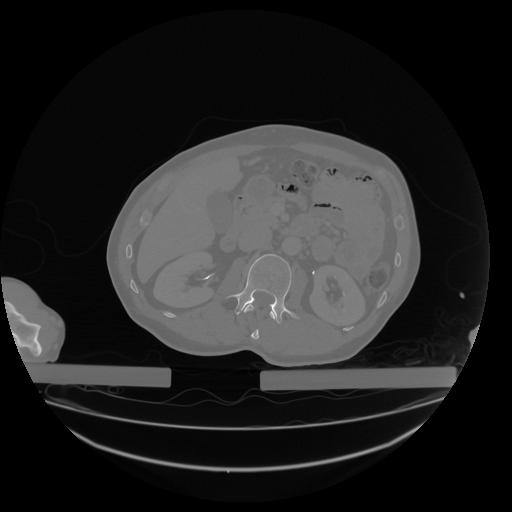

34 CUERPO,CE,Vol,1.0,CUERPO,,